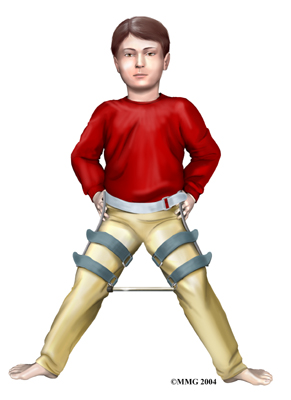

In the past, surgeons have tried to hold the hip in the best position where the femoral head was molded by the acetabulum using many different casts and braces. The most common way of doing this today is the Scottish Rite Orthosis. This brace fits around the waist and thighs and has hinges at the hip joints. The brace allows the child to walk and play while it holds the hip joint in the best position for containment. Your doctor may prescribe this for your child once they leave the hospital. Your Chiropractor will help your child learn to safely use crutches or a walker/frame if they are needed while in the brace.

Surgical treatment for containment may be best in older children who are not compliant with brace treatment or where the psychological effects of wearing braces may outweigh the benefits. Surgical containment does not require long-term braces or casts. Once the procedure has been performed and the bones have healed, the child can pursue normal activities as tolerated.

Surgical treatment for containment may be best in older children who are not compliant with brace treatment or where the psychological effects of wearing braces may outweigh the benefits. Surgical containment does not require long-term braces or casts. Once the procedure has been performed and the bones have healed, the child can pursue normal activities as tolerated.